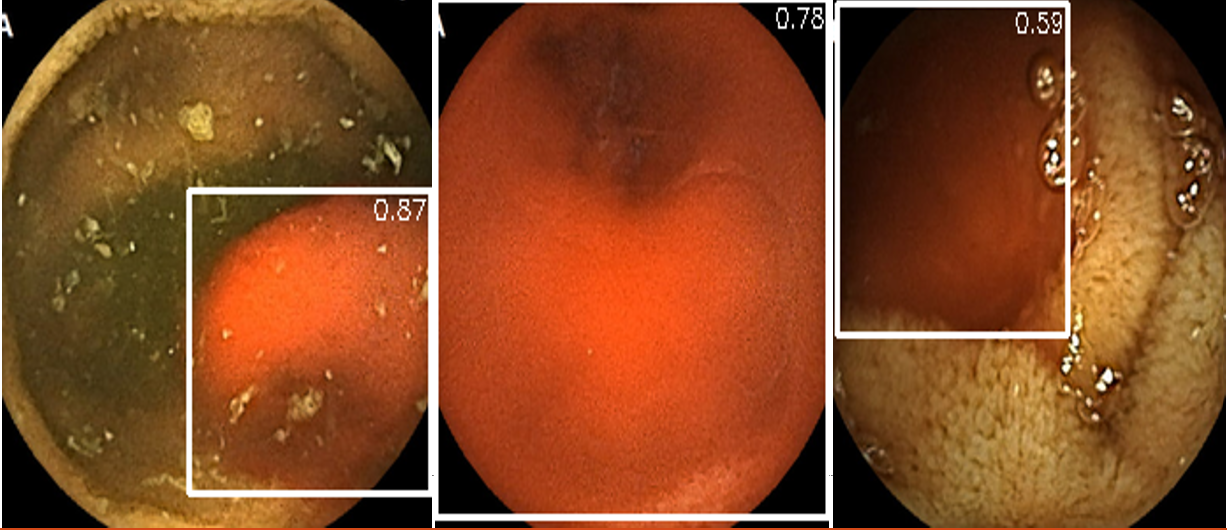

Refer to caption

Figure 4: Detection results on Test Dataset 2 showing bleeding regions (marked by white bounding boxes) with confidence scores of 0.87 (left), 0.78 (middle), and 0.59 (right).